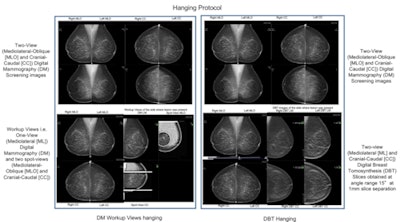

Details of the hanging protocol used for both the digital mammography workup view and DBT assessments. Image courtesy of Suneeta Mall.